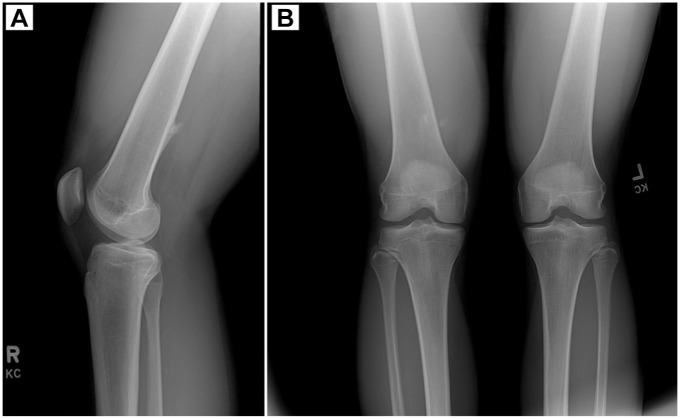

Pseudoaneurysm of the Superficial Femoral Artery Secondary to Exostosis-like Lesion Trauma After Hamstring Tear: A Case Report.